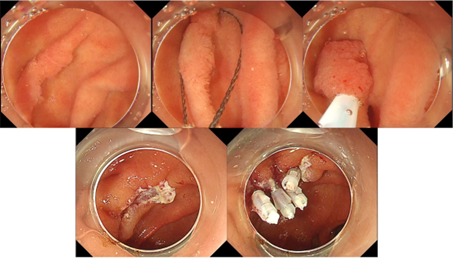

図1:十二指腸がんに対するESD

しかしながら、十二指腸は消化管の中でも特に治療が難しい部位です。腸壁が薄く、治療中の穿孔リスクが高いうえ、治療後に胆汁や膵液が接触することで遅発性の出血や穿孔が起きる可能性も高くなります。術前に行った生検が粘膜下層に強い線維化を引き起こし、切除を困難にすることもあります。特に広範囲の病変を剥離する内視鏡的粘膜下層剥離術(ESD)は、技術的難易度と偶発症のリスクが非常に高い手技です。

これらの課題を克服するため、近年ではさまざまな工夫が導入されています。比較的小さく悪性度の低い腺腫に対しては、電気を使わずに安全に切除できるコールド・ポリペクトミーや、局注を行わず水中で浮かせて切除するアンダーウォーターEMRといった技術が登場し、より安全・簡便な治療が可能になっています。また、ESDにおいても治療中・治療後の管理方法が改良され、成績は着実に向上しています。